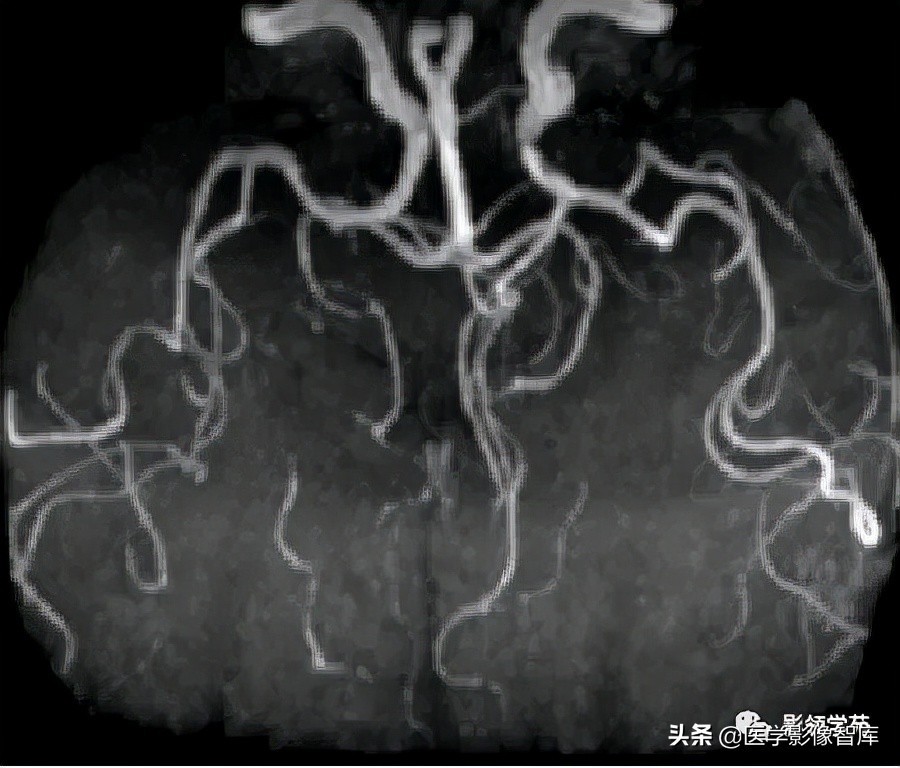

女 58岁,头晕、呕吐,桥脑右前方见一类圆形

高低混合(有血栓)T1及T2信号影,边界清楚、锐利。

明显不均匀强化(瘤内有血栓)。与基底动脉分界不清

头颅CTA:基底动脉起始部血管局部瘤样突起(宽基底),无占位效应。

女 72岁,发现糖尿病3年余

鞍上区见一团块状稍高密度影,边界尚清,密度均匀。

鞍上右上方见一类椭圆形流空影。

病灶明显强化(瘤内血栓未强化),边界清楚,与右侧颈内动脉海绵段分界不清。垂体大小、形态未见异常。